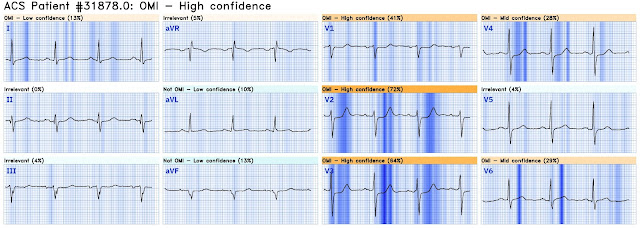

In summary the wide complex tachycardia and the resting ECG should alert you to right ventricular pathology. I put this ECG through the QoH for digitization purposes and the QoH AI algorithm was not fooled by the ST-T changes in this ECG. The interpretation was not OMI with high confidence.